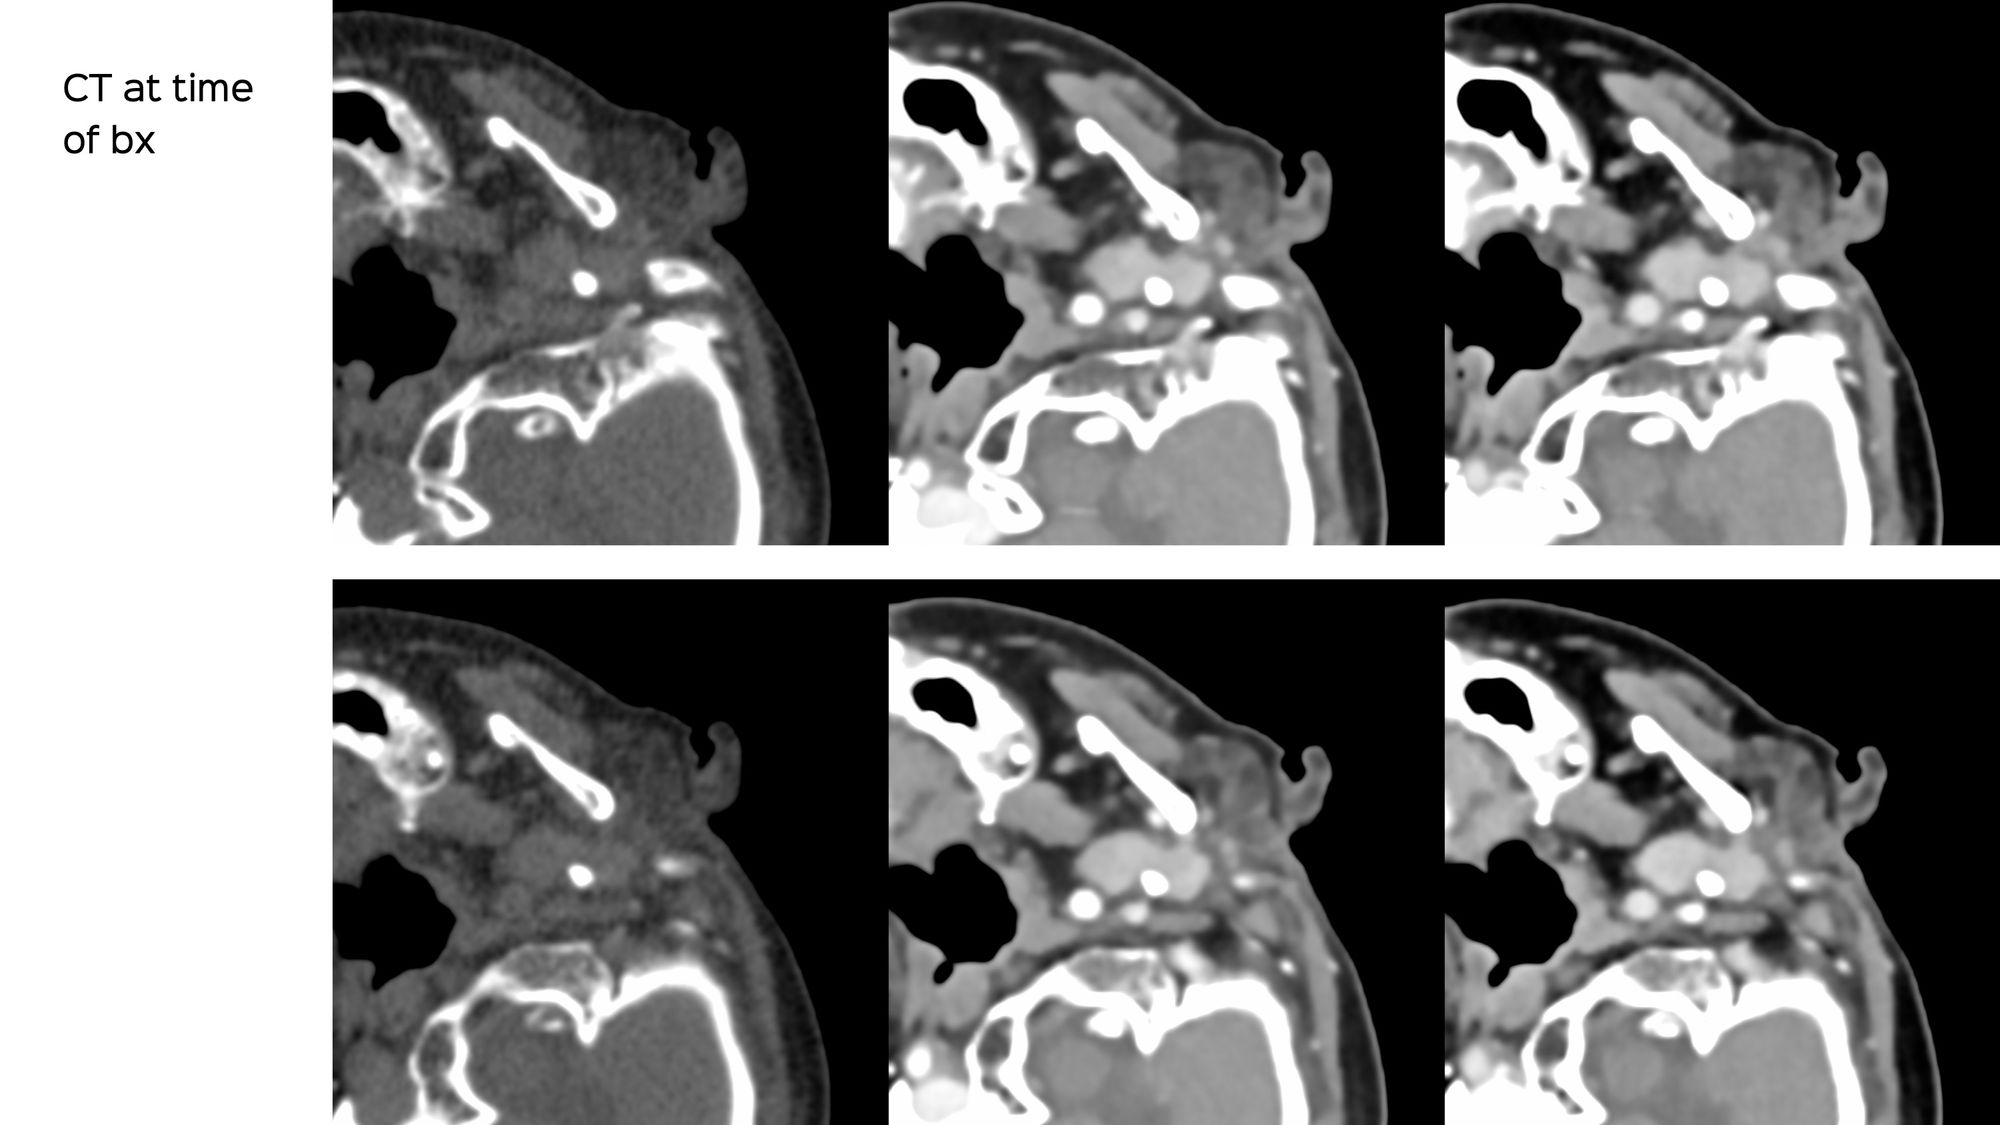

The surgeon asked for a CT guided biopsy. This was the appearance at the time of the biopsy